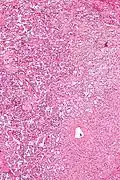

Micrograph of a gangliocytic paraganglioma. H&E stain. | |

A gangliocytic paraganglioma is a rare tumour that is typically found in the duodenum and consists of three components: (1) ganglion cells, (2) epithelioid cells (paraganglioma-like) and, (3) spindle cells (schwannoma-like).[1]

GP consist of three components (1) ganglion cells, (2) epithelioid cells (neuroendocrine-like), and (3) spindle cells (schwannoma-like). The microscopic differential diagnosis includes poorly differentiated carcinoma, neuroendocrine tumour and paraganglioma.[1]